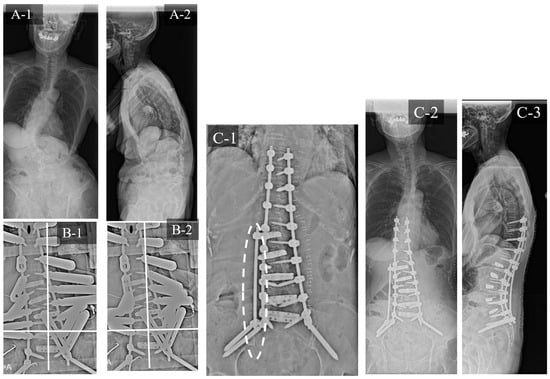

3.1. Case Study 1: RR

3.2. Case Study 2: RR and SD

3.3. Case Study 3: RR and KR